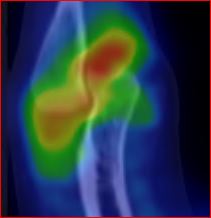

Pacient indikován ortopedem pro scintigraficky (obr.1,2,3) prokázanou synovialitidu pravého loketního kloubu.

/ Obr.1.: SPECT/CT v MIP projekci - zvýšený krevní pool v oblasti synoviální membrány pravého loketního kloubu.